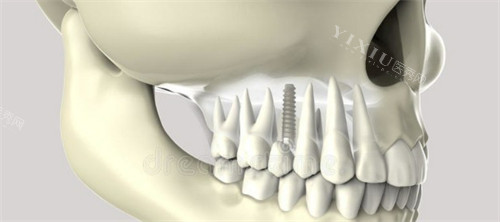

很多网友分享过纠结过程——缺了一颗牙,医生会问选种植牙还是烤瓷牙。种植牙是在缺牙位置的牙槽骨里植入钛合金“人工牙根”,等3-6个月和骨头长稳后,再装牙冠;烤瓷牙则要把缺牙两边的健康牙齿磨小一圈,做个连在一起的“桥体”,把假牙固定在磨小的邻牙上。

1. 牙槽骨条件:种植牙需要足够骨量,骨量不足可能要植骨;烤瓷牙对骨量要求低。